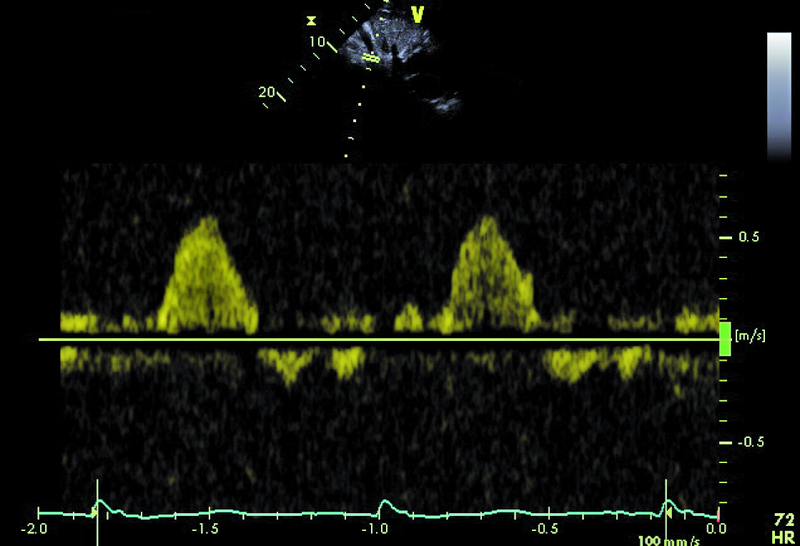

Kobieta, lat 41. Jakie patologie można rozpoznać na zamieszczonych rycinach?

2. Dwupłatkowa zastawka aortalna (ryc. 2).

4. Ciężka dysfunkcja skurczowa lewej komory (ryc. 3-5).

5. Niedomykalność zastawki aortalnej (ryc. 5, 6).